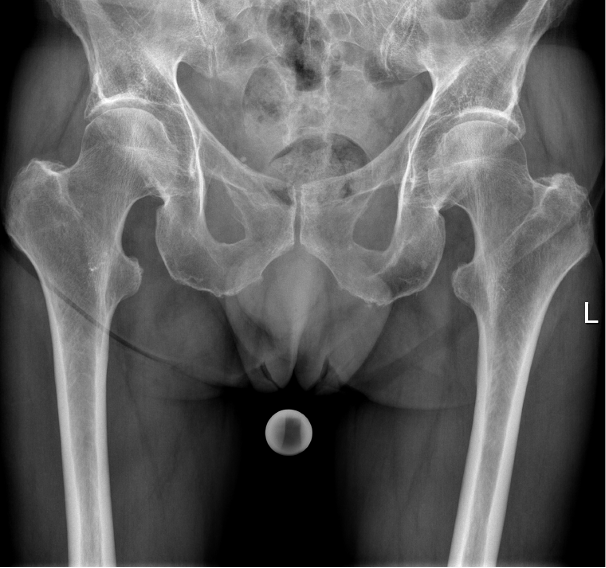

Ein 78-jähriger Patient stellt sich mit dem Rettungsdienst in der Nofallambulanz vor. Vor 4,5 Wochen war er bei Blitzeis auf das Gesäß gestürzt und hatte Schmerzen bemerkt die vor allem in der rechten Gesäßhälfte lokalisiert waren. In einer zu dem Zeitpunkt durchgeführten Röntgendiagnostik konnte keine Fraktur festgestellt werden. Nun stellt sich der Patient mit progredienten und nun auch in der linken Hälfte lokalisierten Schmerzen vor, die bis in den linken Oberschenkel ausstrahlen. Das Gehen sei schmerzhaft, die Kraft und Sensibilität sei jedoch vollständig in den unteren Extremitäten erhalten.

Vorerkrankungen: Osteoporose mit bekannten osteoporotische LWS-Frakturen